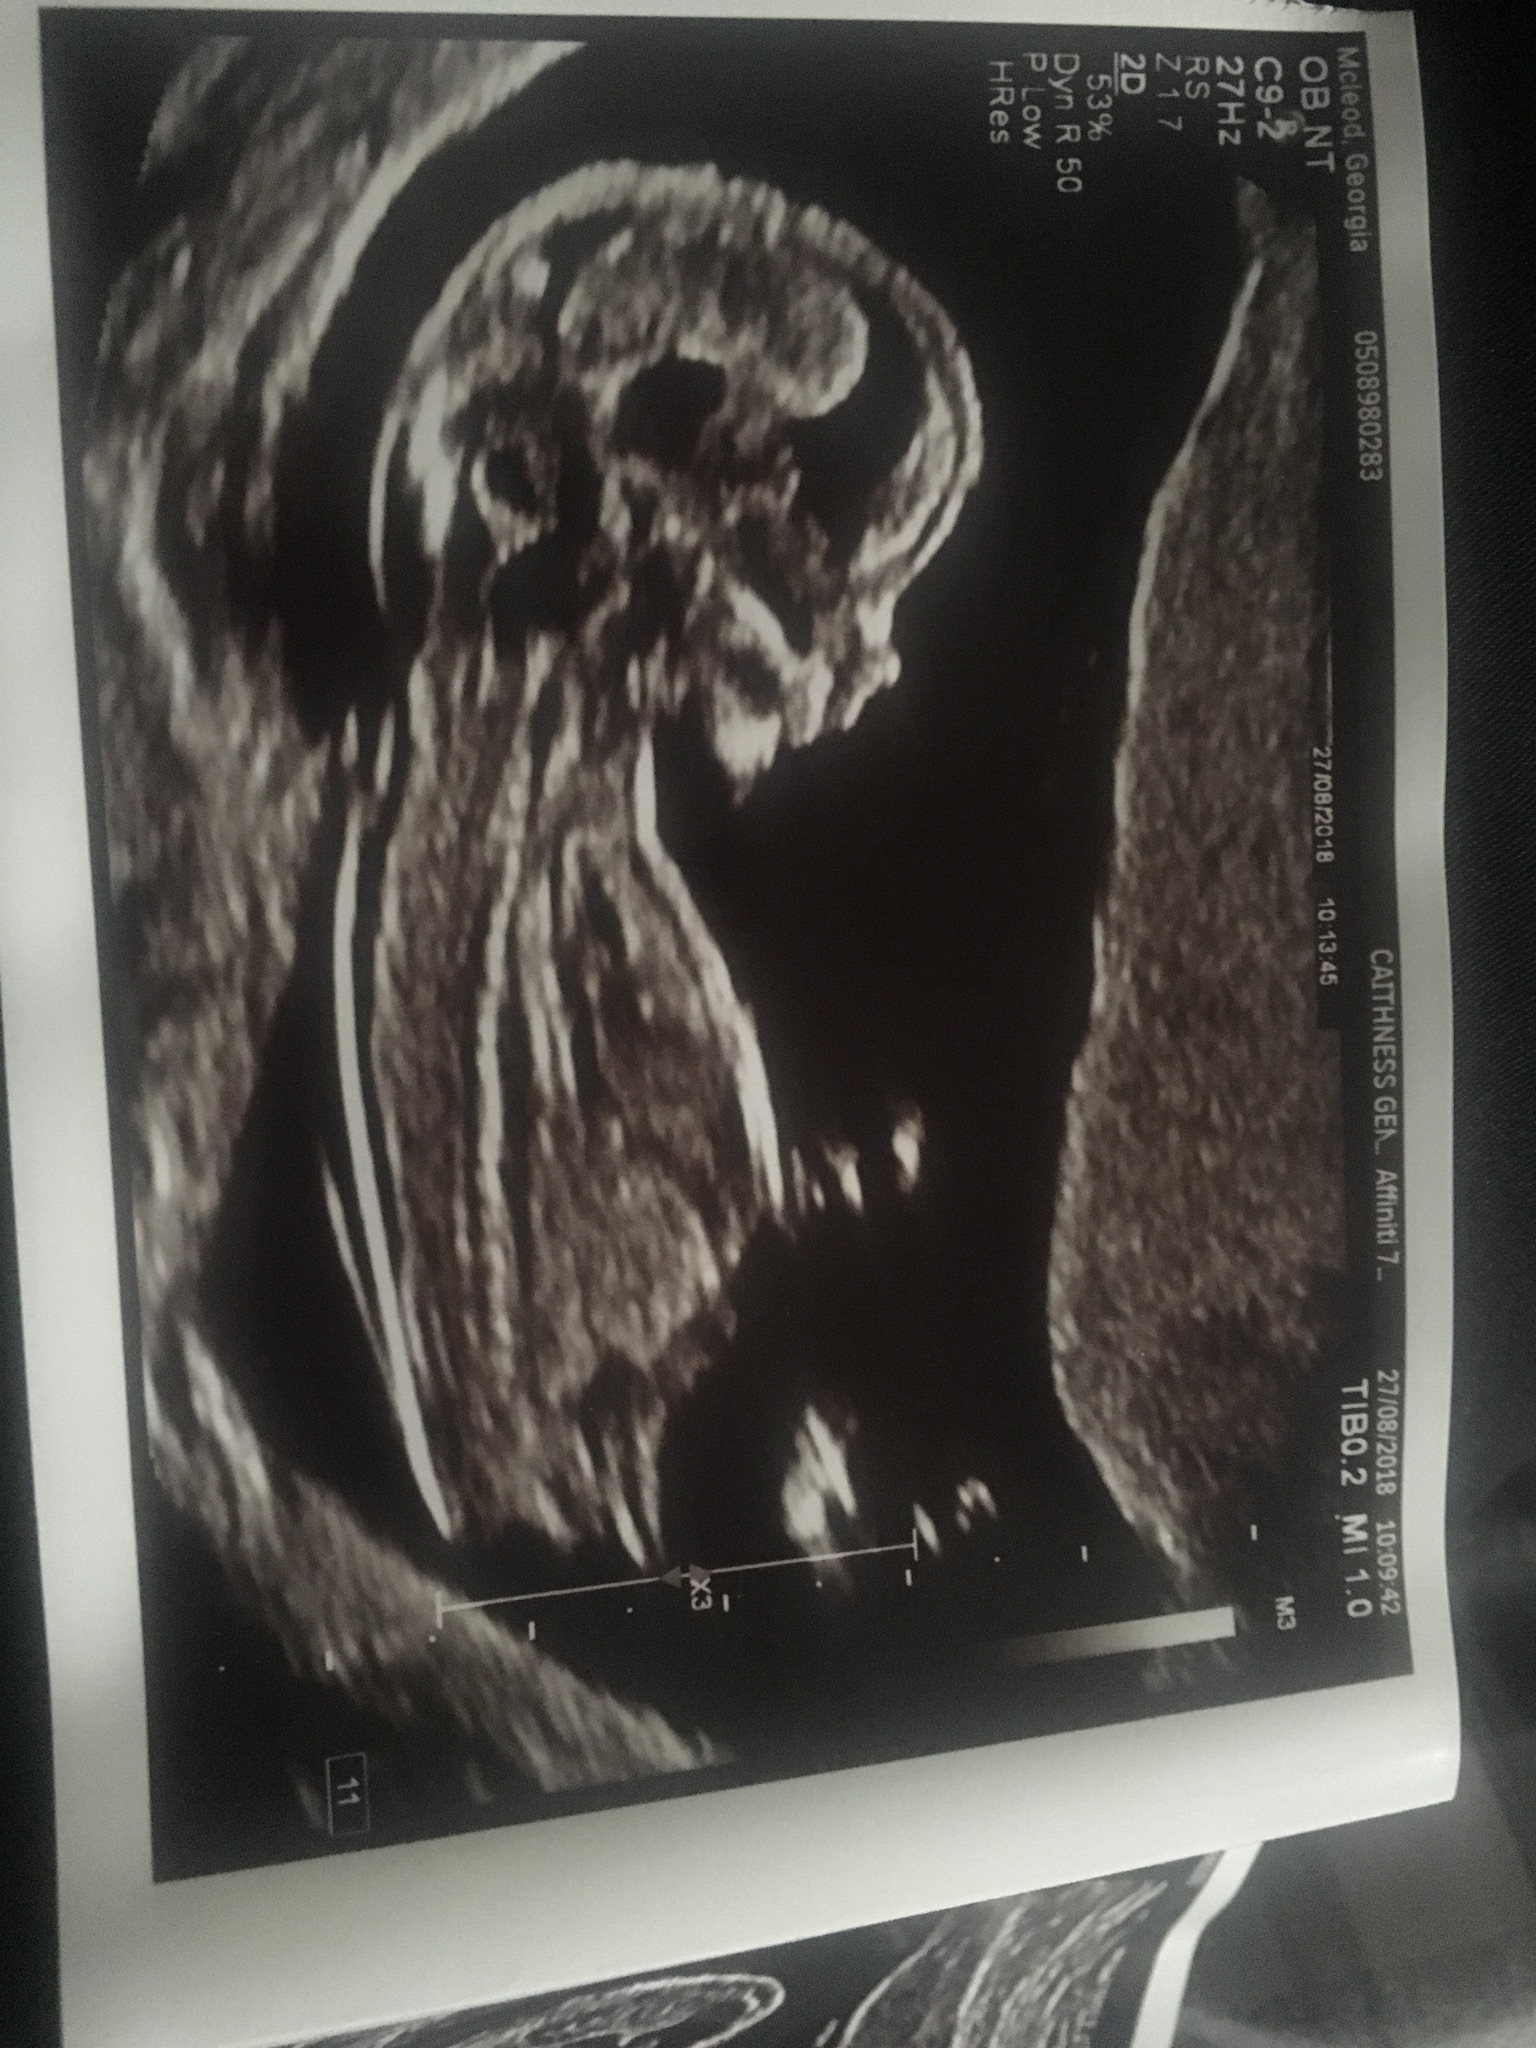

Is there a nub in this picture?Attachment 40237